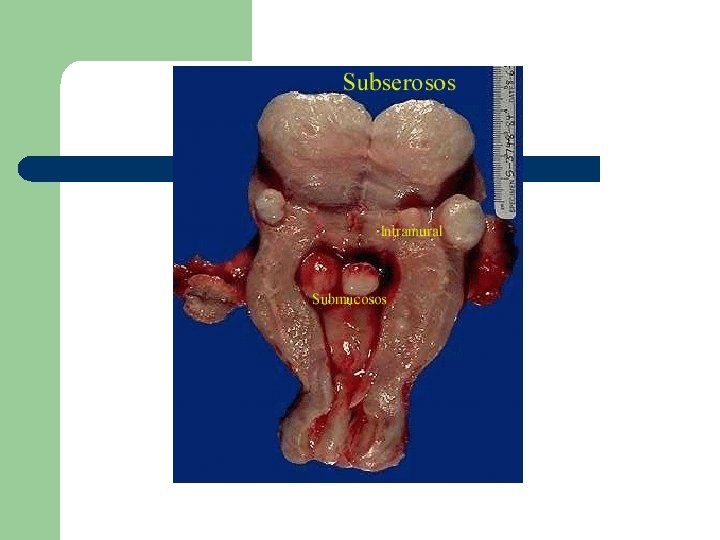

Localización

Localización l Miomas subserosos – – – 40% Situados bajo el peritoneo visceral uterino Alcanzan gran tamaño siendo poco sintomáticos. Puede ser pediculado Si se implanta en un órgano extragenital: mioma parásito

Localización l Miomas intramurales – – – Son los más frecuentes (55%) Proliferan en la porción central del endometrio. Al aumentar de tamaño se convierten en subserosos o submucosos

Localización l Miomas submucosos – – 5 -10% Protuyen hacia la cavidad uterina Los más sintomáticos Pueden ser pediculados y prolapsarse a través del orificio cervical (mioma parido)